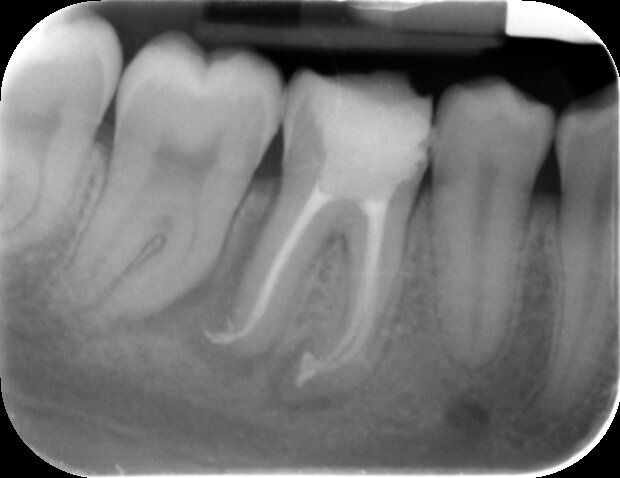

Pre-op PA of the LR6 shows a mesial cavity opening into the pulp, the mesial canals seem sclerosed towards the apex, this is further complicated by an acute curvature